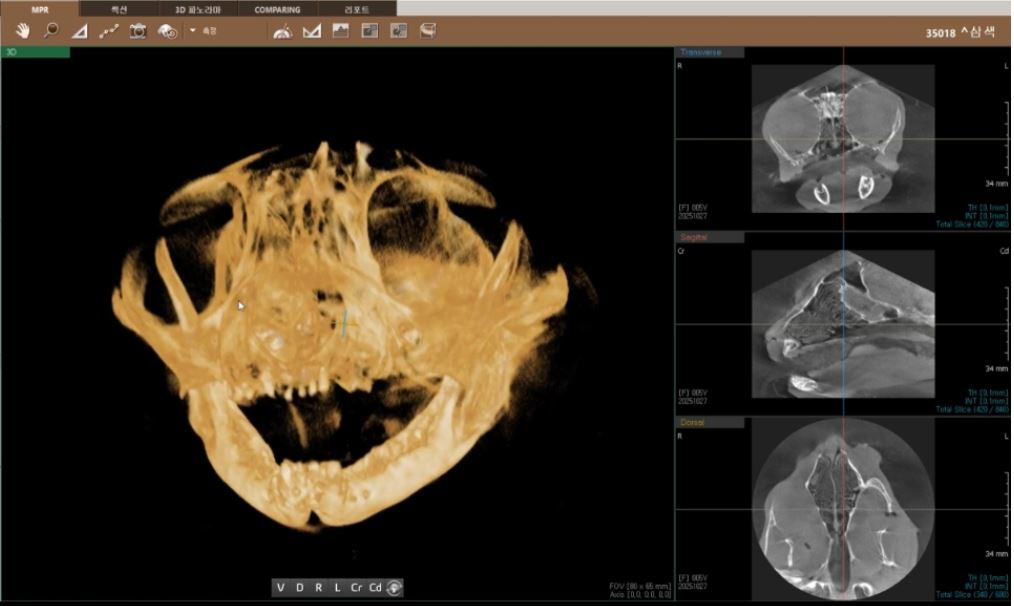

| 치료과정 | 선생님께서 삼색이 입안 사진을 보여주셨는데 밖에서 보여지는 것, 생각했던 것보다 심해 보였습니다. 피가 고여있고 점막궤양화가 진행되고 있다고 설명해주셨습니다. 치료 후 방사예정이라 송곳니라도 남기고 싶었지만 선생님께서 전발치를 권하셨고, 선생님 뜻에 따라 윗 앞니만 제외하고 전발치를 했습니다. 힘든 수술이었지만 아이가 잘 견뎌준것 같습니다. 3일 입원하며 통증 조절 시키고, 나머지 보름동안은 저희 집 케어장에서 케어하며 처방받은 스테로이드제와 항생제를 먹였습니다. 혀가 들어가고, 입 주변이 깨끗해지고, 그루밍을 할 수 있게되더니 털 상태까지 좋아지는 모습을 볼 수 있었습니다. 밥도 잘 먹어주어 너무 다행이었습니다. 원래도 말랐던 아이라 치료 기간 동안 많이 먹고 회복할 수 있도록 습식을 충분히 주었고, 방사 전에는 건사료도 잘 먹는 모습을 확인했습니다. 미모도 다시 되살아났습니다. |

선생님께서 삼색이의 입 안을 촬영해 보여주셨을 때, 겉에서 보던 모습과는 비교할 수 없을 만큼 상태가 심각해 보였습니다. 피가 고여 있었고, 점막이 궤양으로 진행되고 있다고 설명해주셨습니다. 치료 후 방사 촬영을 예정하고 있어 최소한 송곳니라도 남기고 싶었지만, 선생님께서는 전발치를 권하셨고 아이에게 가장 좋은 방향이라는 판단 아래 윗 앞니만 남기고 전발치를 진행했습니다. 긴 수술이었음에도 삼색이가 끝까지 잘 버텨준 것이 너무 대견했습니다.수술 후 3일간 입원하며 집중적으로 통증 조절을 받았고, 이후 보름 동안은 저희 집 케어장에서 처방받은 스테로이드제와 항생제를 복용하며 회복을 이어갔습니다. 시간이 지나면서 혀가 다시 잘 들어가고, 입 주변의 염증이 눈에 띄게 가라앉기 시작했습니다. 그루밍도 가능해지면서 털 상태까지 점점 좋아지는 모습을 보며 안심할 수 있었습니다. 무엇보다 밥을 잘 먹어주는 것이 큰 힘이 되었습니다. 원래 마른 체질이라 영양을 잘 채워줘야 한다는 마음으로 치료 기간 동안 습식 사료를 충분히 제공했고, 방사 전에는 건식 사료도 문제없이 먹는 모습을 확인했습니다. 그렇게 회복이 진행되면서 삼색이의 예쁜 모습과 생기까지 다시 살아나는 것을 보며 정말 다행이라고 느꼈습니다.

치아 엑스레이 발치 전, 후 사진입니다.